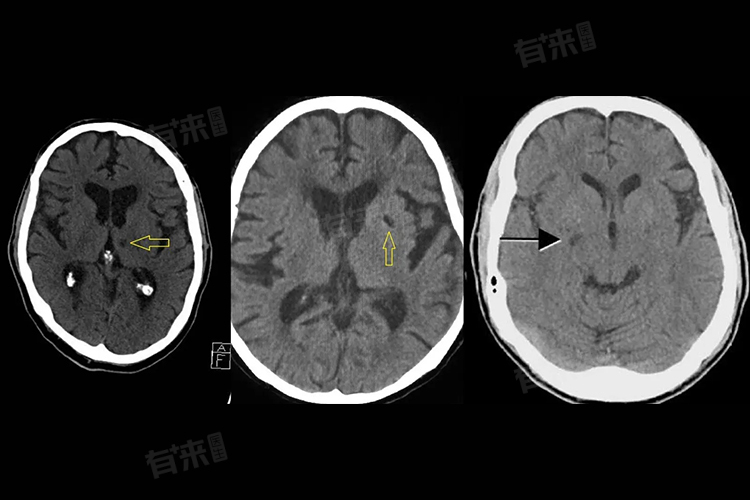

- 腔隙性脑梗塞的诊断主要依赖于影像学检查,如头颅CT和核磁共振,能够清晰地显示梗死病灶的位置和大小。医生还会详细询问患者的病史,了解患者的症状表现,以及进行必要的血液检查等,以综合判断患者的病情。